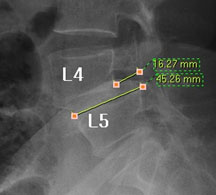

뼈가 앞으로 밀려나갔다고 하니 척추가 당장이라도 주저 앉을 것 같고, 한없이 밀려나갈 것 같지만 일반적으로 밀려나간 뼈는 대부분 1-2단계(25~50%) 정도 밀려나간 상태에서 안정화되는 경향을 보이기 때문에 그 자체로는 문제가 되지 않습니다.

즉, 척추전방위증은 통증을 일으키는 원인질환(디스크, 협착증)을 치료하는 것이 척추 뼈를 더 이상 앞으로 밀려나가지 않게 하는 치료라고 볼 수 있습니다. 모커리는 뼈가 50% 이상 밀려나간 2단계의 척추전방위증도 비수술로 치료하고 있으며, 이러한 한방치료 효과를 객관적으로 검증하여 유명학회 및 논문에 계속해서 발표하고 있습니다.

모커리한방병원은 2013년 1월부터 2014년 3월까지 척추전방위증으로 입원한 환자를 대상으로 치료 전•후를 비교분석한 결과, 복합척추치료 약 3주 후 환자가 느끼는 허리와 엉덩이 통증지수가 7.1에서 3.1로 줄었으며, 통증 없이 걸을 수 있는 거리 역시 193m에서 568m로 약 3배 가량 증가했습니다. 이번 연구결과를 계기로 50% 정도 밀려나간 2단계의 척추전방위증 환자들도 수술 없이 충분히 치료될 수 있다는 것이 객관적으로 검증되었습니다.

모커리한방병원은 50% 정도 밀려나간 2단계의 척추전방위증 환자를 대상으로 약 3주간의 입원집중치료를 실시한 결과, 입원 시보다 80% 이상 통증이 감소되어 치료되었습니다. 통증 없이 걷는 시간도 약 3배 정도 증가되어 단기간에 수술 없이 높은 치료효과가 나타났다는 것을 대한침구의학회에 발표하였습니다. 50% 정도 밀려나간 2단계의 중증 척추전방전위증 환자이면서 심한 척추협착증 증상을 나타내는 환자를 치료한 결과입니다.